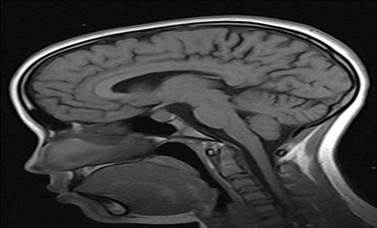

- Resonancia magnética nuclear (RMN) No 2755: Silla turca aumentada de tamaño, ocupada por imagen isointensa de la glándula hipófisis en T1 y T2, que mide 20 mm de diámetro mayor, con el aspecto de macroadenoma (Figura 2).